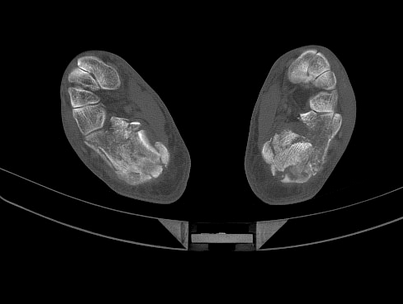

X射线及CT检查所见是诊断爆裂性眼眶骨折的重要方法。90%以上的眼眶骨折可用X射线及CT检查得到确诊。根据眼眶X射线平片和CT扫描照片,结合上述临床特征,可以确定眶底骨折的部位、形态、范围、有无眶内容物脱出,以及是否合并眶内、外、上壁骨折。必要时可在眶底部注入阳性对比剂以显示骨折破坏区。在典型病例的X射线和CT照片上可以看到上颌窦顶部变形、眶底下沉、眶内软组织陷入上颌窦的阴影和鼻窦内碎骨片阴影。CT冠状扫描可将下直肌与眶底的关系分为3型:①游离型:肌束未贴附骨壁;②钩挂型:肿胀的肌肉部分位移,与骨折区贴附;③脱陷型:肿胀的下直肌束夹在碎骨之间。 CT检查还可将爆裂性骨折分为眶底型、泪滴型、隅角型和复合型4型。